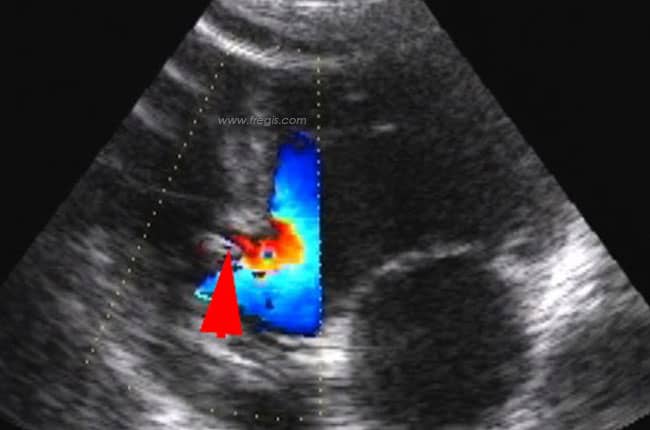

L’échocardiographie permet de visualiser directement la communication interventriculaire, d’en apprécier la localisation, la taille et l’importance. Elle permet aussi de déterminer le sens du shunt et d’apprécier les répercussions éventuelles de la CIV sur la fonction cardiaque.